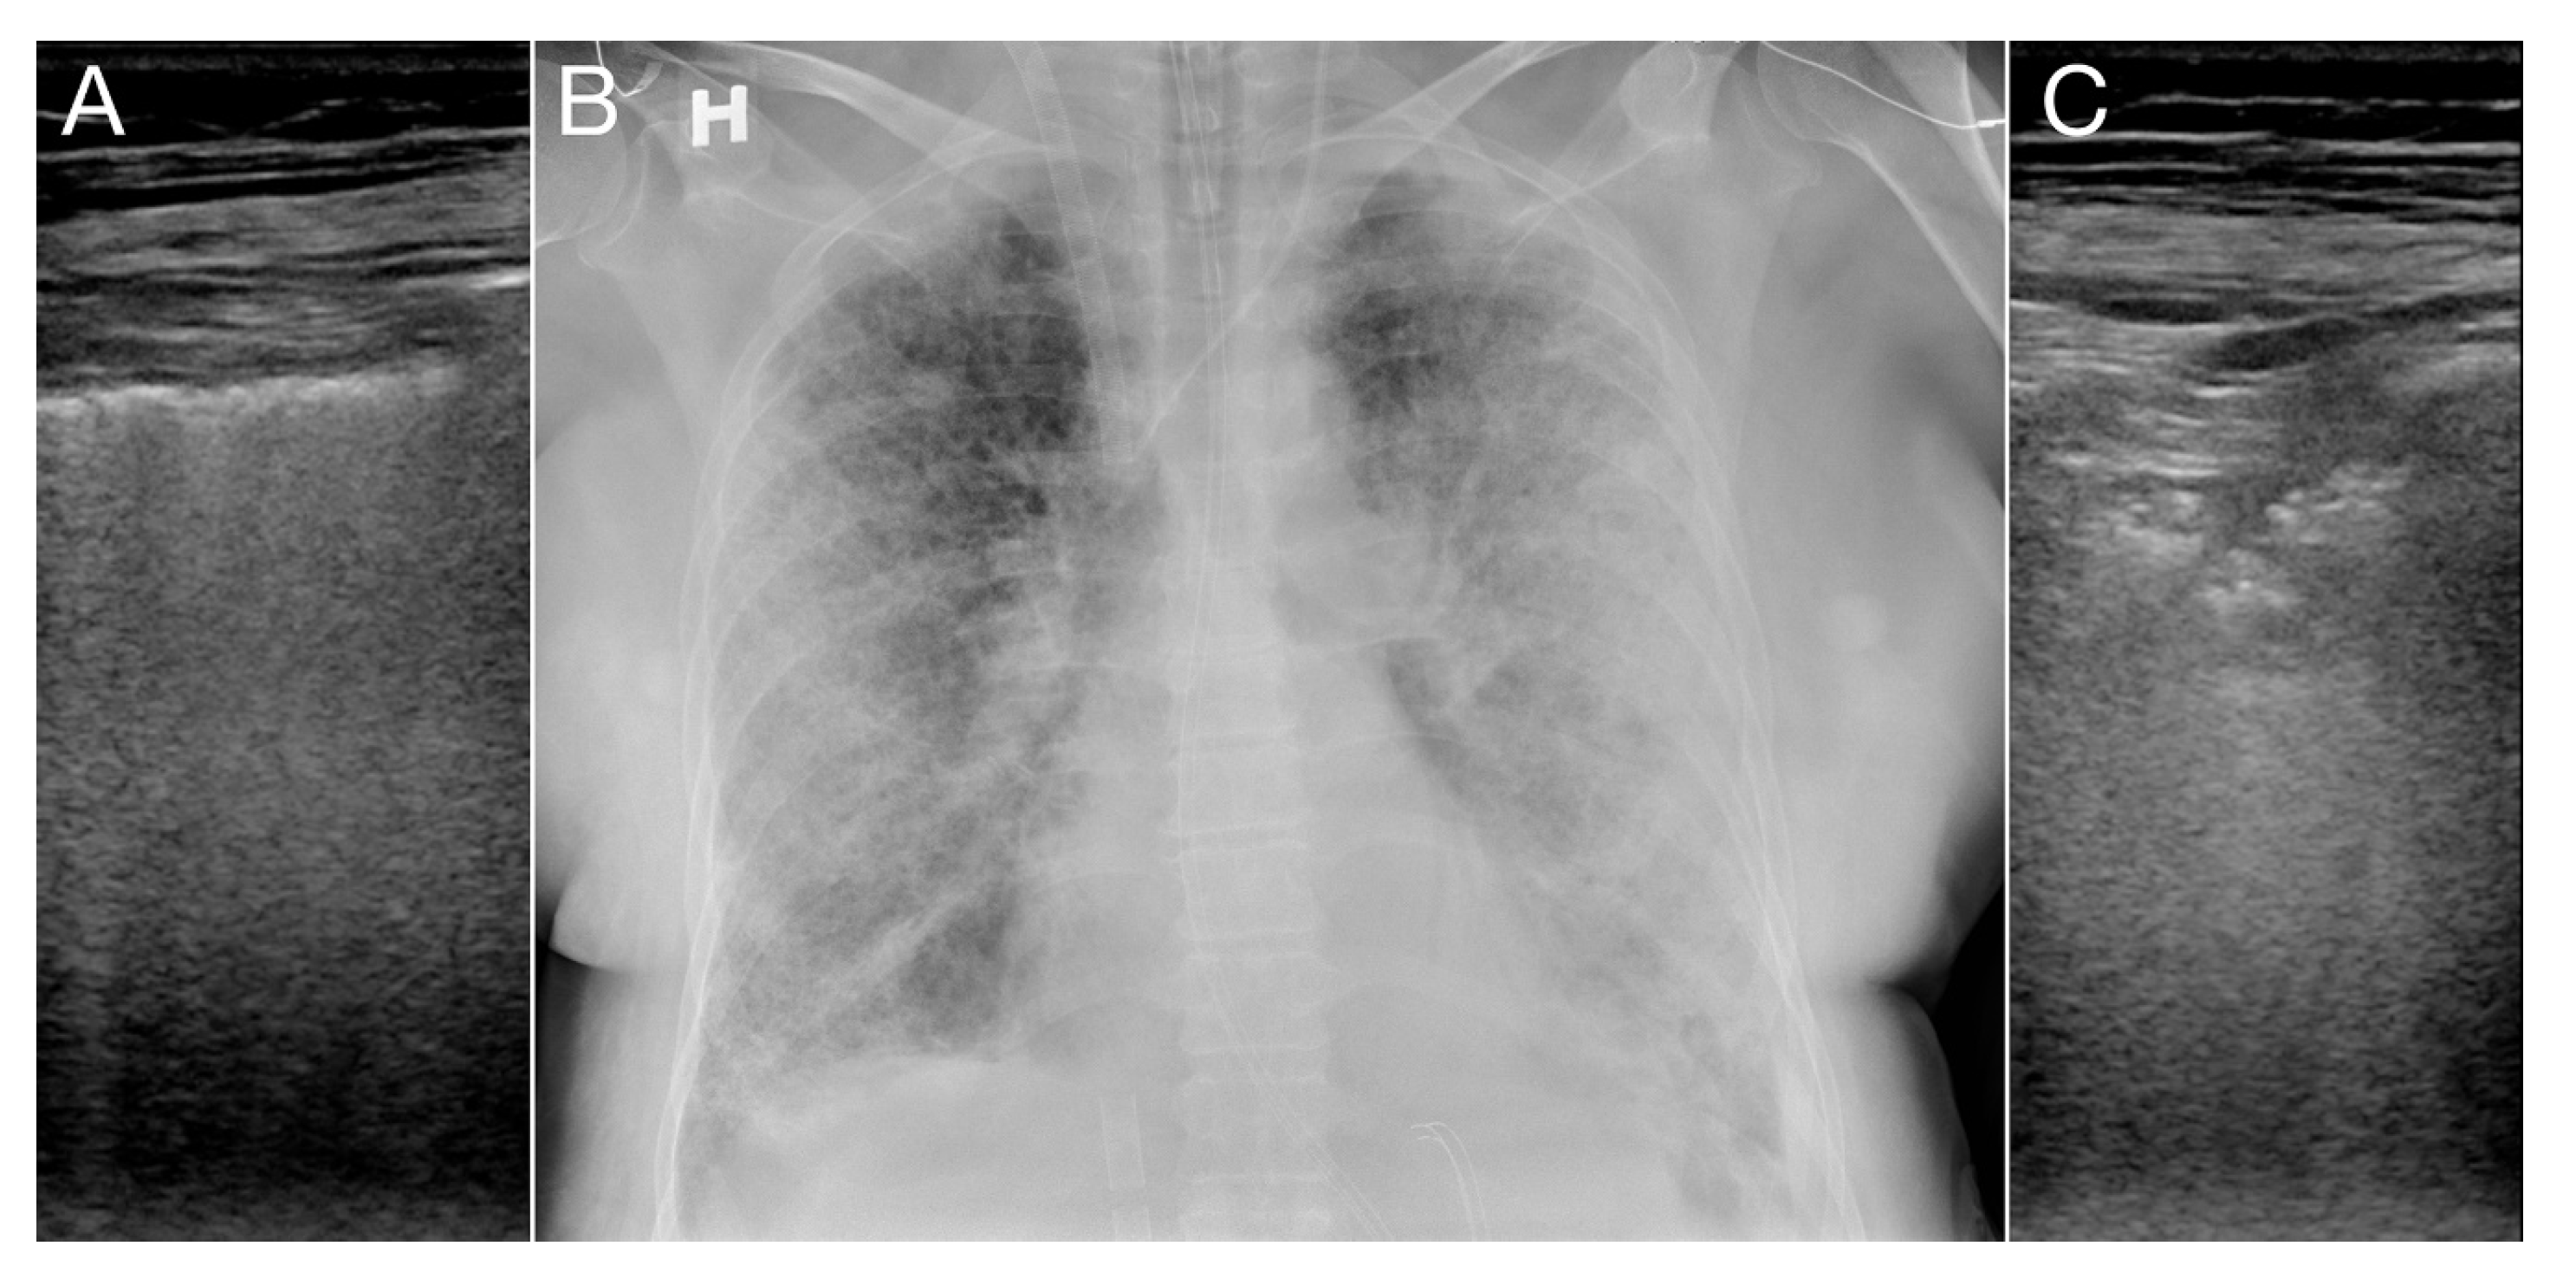

Diagnostics Free Full Text Covid 19 Assessment With Bedside Lung Ultrasound In A Population Of Intensive Care Patients Treated With Mechanical Ventilation And Ecmo Html

www.mdpi.com